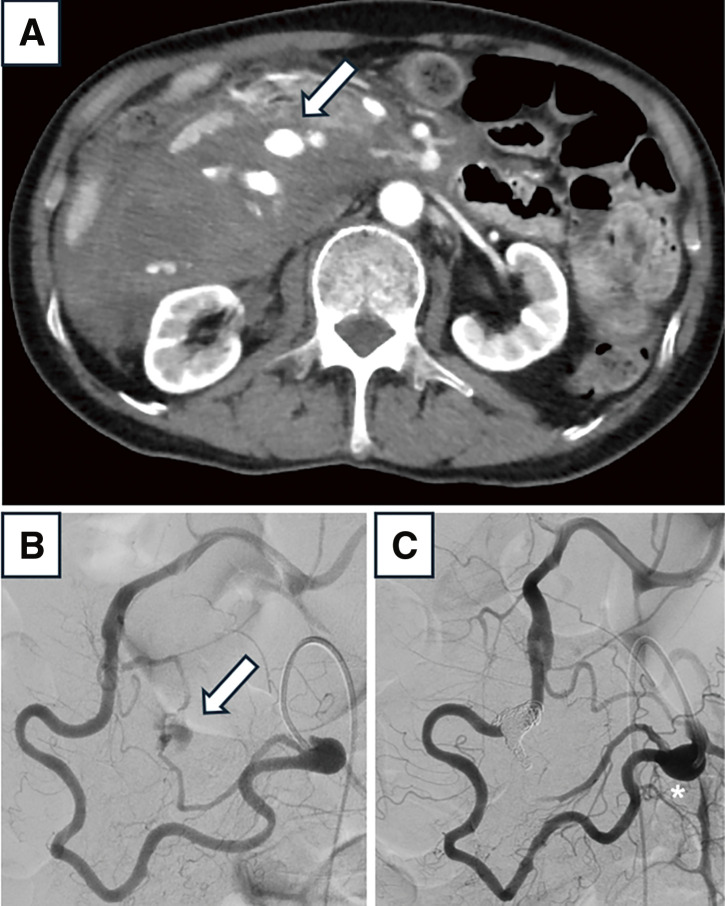

Herein, we describe the case of a 72-year-old man who presented with a residual inferior pancreaticoduodenal artery aneurysm following the rupture and treatment of a superior pancreaticoduodenal artery aneurysm. Open surgery for pancreaticoduodenal artery aneurysms requires carefully planned vascular reconstruction to prevent organ ischemia and minimize pressure changes caused by fluctuations in mechanical stress. Additionally, in cases of rupture, factors such as the patient's condition, presence of hematoma and adhesions, and pressure changes resulting from prior transarterial embolization must be considered. This case report outlines the surgical strategy employed for managing the residual inferior pancreaticoduodenal artery aneurysm.